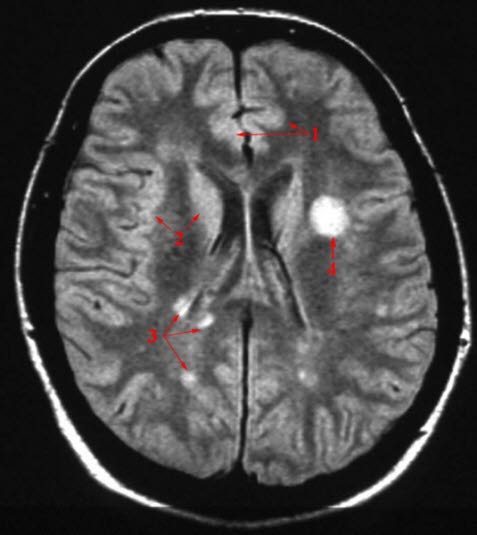

Sykehistorien med de typiske symptomer hos forholdsvis unge mennesker vil ofte gi mistanke om sykdommen. I tidlig fase kan det være vanskelig å påvise tegn til sykdom ved vanlig legeundersøkelse, men etter en tids sykdom blir funnene som regel tydelige. Diagnosen kan stilles på grunnlag av sykehistorie og funn ved legeundersøkelse alene. I praksis blir det alltid også utført MR-undersøkelse av hjernen. MR-forandringene ved MS er typiske. MR er også nyttig for å utelukke andre årsaker til symptomene. En undersøkelse av ryggmargsvæsken kan også vise forandringer som bekrefter diagnosen.